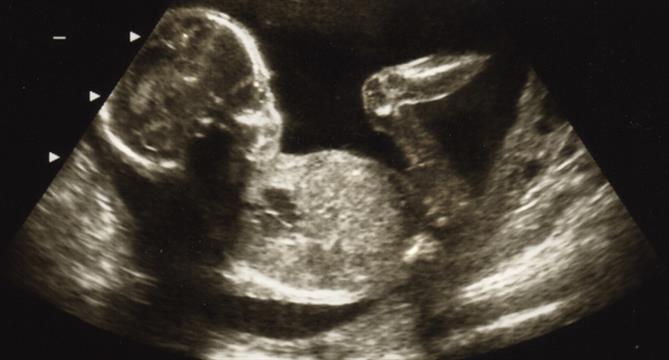

Saya baru saja menjalani kuretase, karena blighted ovum. Apa arti istilah ini dan kapan saya bisa pulih kembali dan berhubungan dengan suami? ... read more